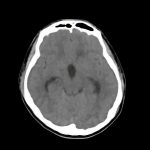

症例 '15年2月

No.

※ 画像をクリックすると拡大表示します。症例No.は平成29年から起算しています。

年_番号

手術年月

患者年齢

’15_16

'15年2月

20代

病名

術式

備考

頭蓋咽頭腫

断層撮影

手術前

1

手術前2

手術後